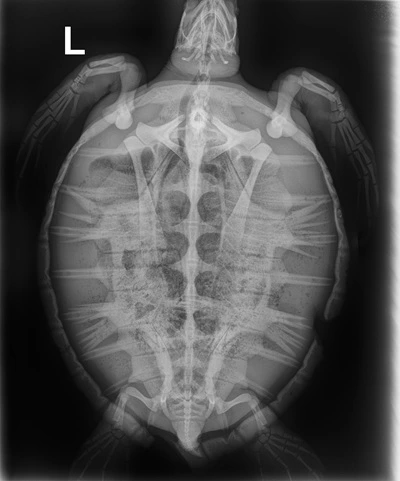

4.55kg juvenile Atlantic Green

Patient Injuries

Flippers: Broken nail on Right rear flipper, Algae build up on soft tissue of rear flippers